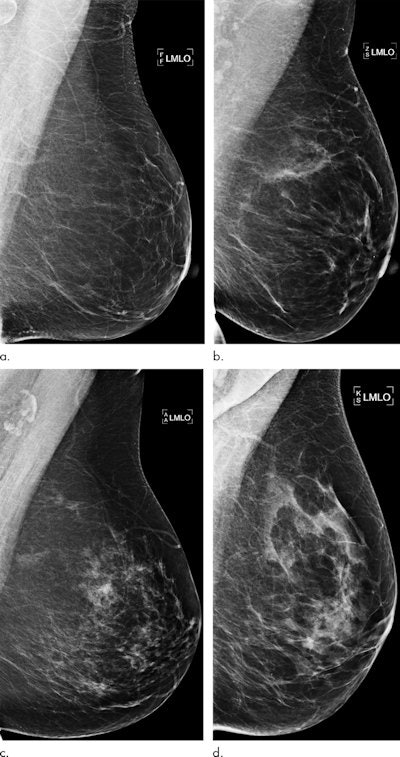

High breast density is considered a risk factor for cancer, but current prediction models may not fully exploit all the rich information found in mammography images, according to the researchers. This additional information could potentially identify those women who would benefit from additional screening with MRI.

To see if deep learning could help, the researchers trained and validated an Inception-ResNet-v2 deep neural network using over 11,000 cases diagnosed from women ages 40 to 74 who had received mammograms in the Karolinska University Hospital system between 2008 and 2012. All of the women received screening mammography on full-field digital mammography systems from Hologic.

After analyzing the mammography images, the woman's age at image acquisition, and four acquisition parameters, the deep-learning model output a risk score. The researchers then tested the algorithm on a separate test set of 2,283 women, which included 278 breast cancer cases diagnosed between 2013 and 2014 and within one year of the negative mammogram.

The authors also compared the performance of the algorithm with a risk model based on the age-adjusted percentage of breast density, as well as a risk model based on the age-adjusted dense area of the breast. The density-based measures were calculated using version 10.6 of the publicly available Laboratory for Individualized Breast Radiodensity Assessment (LIBRA) automated breast density estimation software developed by the University of Pennsylvania.